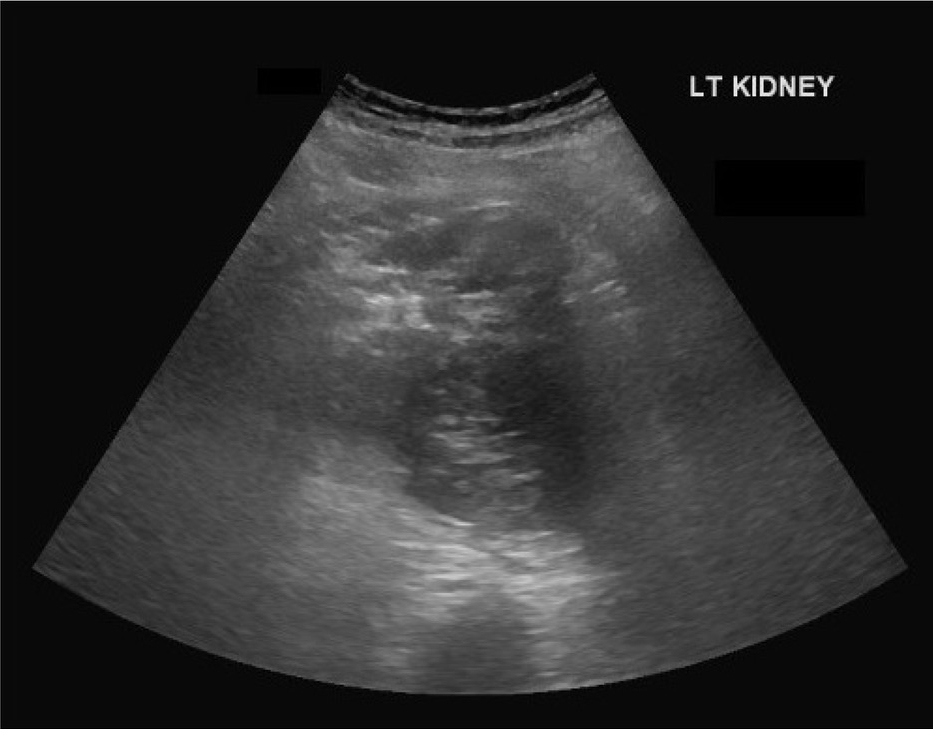

The patient required another 3 units of packed red cell transfusions in our hospital after admission. He subsequently underwent an ultrasound abdomen that revealed a significant collection around the left kidney (Figure 1). A CT abdomen without contrast was arranged due to his AKI and it revealed a 10 cm × 8 cm perinephric hematoma, which had completely distorted the renal mass and the cortex (Figure 2).

US KUB showing left kidney with loss of corticomedullary differentiation with a mass of mixed echogenicity.